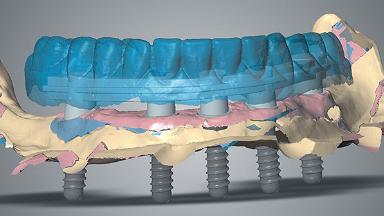

Rehabilitating an Edentulous Maxilla with a Conventional Removable Denture and an Edentulous Mandible with a Fixed Dental Prosthesis Using s-CAIS

This case describes a partial digital workflow in the treatment of a patient with a terminal dentition. It features virtual planning of static computer-aided implant surgery (s-CAIS) and CAD/CAM interim prostheses.

A 72-year-old male patient was referred to the prosthodontic clinic for possible implant treatment. He presented with a partially edentulous maxilla and mandible. The clinical and radiographic examination showed generalized chronic severe periodontitis with tooth mobility, dental caries, and direct composite restorations in three teeth. Pre-treatment periapical and panoramic radiographs revealed horizontal bone loss associated with all remaining teeth and vertical bone loss associated with the anterior teeth and confirmed the presence of generalized carious lesions.